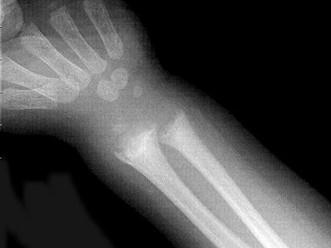

男,2岁,关节浮肿,请结合图像,选出最可能的诊断 ( )A、维生素C缺乏症B、维生素D过多症C、MPSD、维生素D缺乏症E、肾性骨病

问题 男,2岁,关节浮肿,请结合图像,选出最可能的诊断 ( )

选项 A、维生素C缺乏症 B、维生素D过多症 C、MPS D、维生素D缺乏症 E、肾性骨病

答案 E